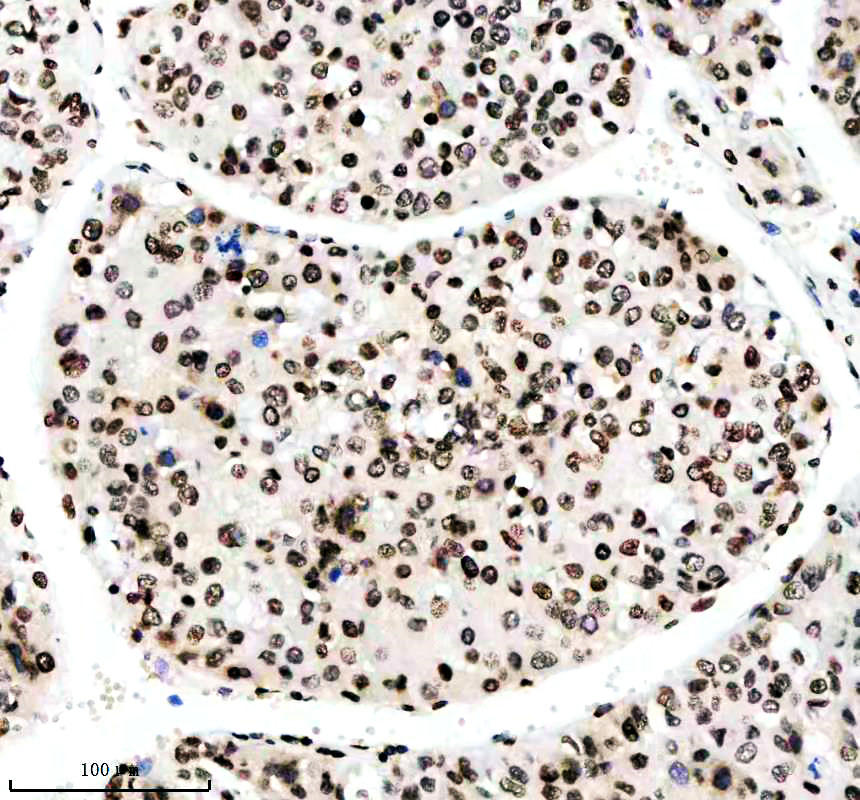

IHC analysis of Histone H3 (acetyl K14) using anti-Histone H3 (acetyl K14) antibody (BM4151) .

Histone H3 (acetyl K14) was detected in a paraffin-embedded section of human liver cancer tissue. The tissue section was incubated with rabbit anti-Histone H3 (acetyl K14) Antibody (BM4151) at a dilution of 1:200 and developed using HRP Conjugated Rabbit IgG Super Vision Assay Kit (Catalog # SV0002) with DAB (Catalog # AR1027) as the chromogen.

IHC analysis of Histone H3 (acetyl K14) using anti-Histone H3 (acetyl K14) antibody (BM4151) .

Histone H3 (acetyl K14) was detected in a paraffin-embedded section of human liver cancer tissue. The tissue section was incubated with rabbit anti-Histone H3 (acetyl K14) Antibody (BM4151) at a dilution of 1:200 and developed using HRP Conjugated Rabbit IgG Super Vision Assay Kit (Catalog # SV0002) with DAB (Catalog # AR1027) as the chromogen.